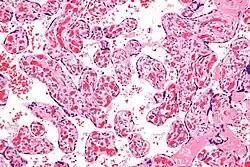

Micrograph of a chorangiosis. H&E stain.

Chorangiosis is a placental pathology characterized by an abundance of blood vessels within the chorionic villi.

It is diagnosed by a microscopic examination of the placenta.

Commonly used criteria from Altshuler[2][3] are: "a minimum of 10 villi, each with 10 or more vascular channels, in 10 or more areas of 3 or more random, non-infarcted placental areas when using a ×10 ocular." The Altshuler criteria are not theoretically rigorous, as they do not define the area. Normal villi have up to five vascular channels.[3]